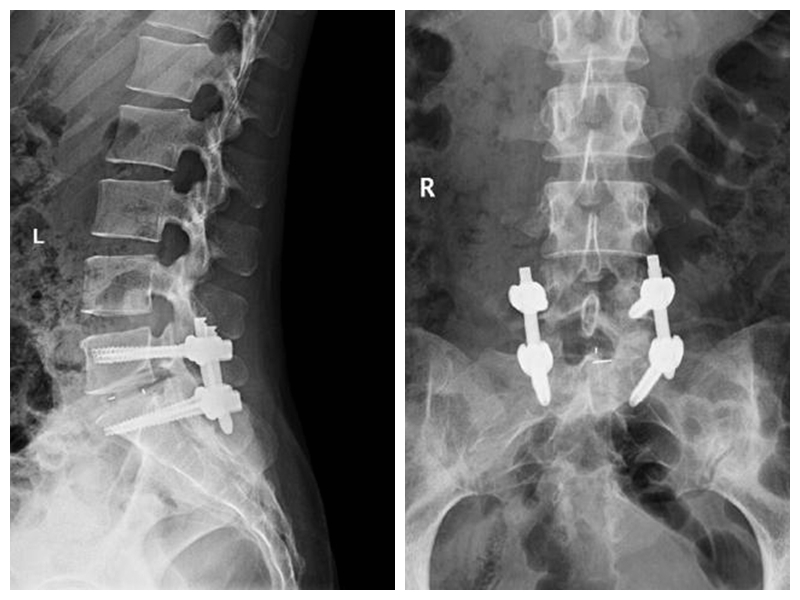

经皮椎体成形术及球囊复位、椎体后凸成形术

经皮椎体成形术及球囊复位、椎体后凸成形术适用于老年性骨质疏松性椎体压缩骨折及肿瘤性病理性压缩骨折。手术创伤小,术后疼痛缓解迅速、恢复时间短,疗效可靠。使患者及早下床活动,改善患者的生活质量,减轻患者家庭及社会的负担。

典型病例:患者刘**,女,70岁,因“在家滑倒摔伤腰背部疼痛活动受限2天”步行入院。查体:腰3、4棘突压痛,椎体及椎旁压痛明显,双下肢肌力、感觉正常。

术后第1天患者下地行走,腰痛明显缓解。(骨科二区 孙进)